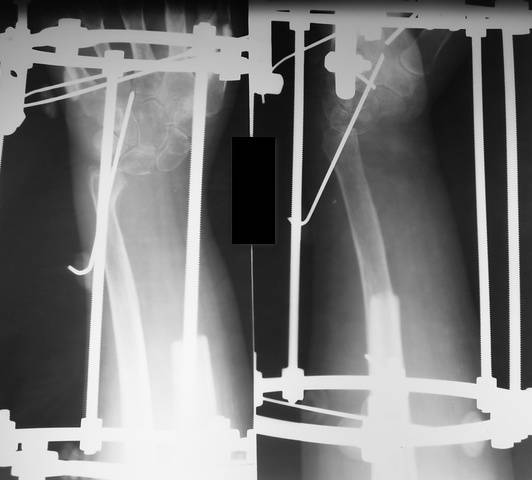

Больной К., 39 лет : в декабре 2006г. выявлена остеобластокластома лучевой кости. Диагноз подтвержден гистологически.

Выполнена краевая резекция с замещением гидроксиапатитом. В сентябре 2007г. рецедив опухоли с бурным ростом. Выполнена резекция н/3 лучевой кости с фиксацией в аппарате. Дефект 11см. На контрольных рентгенограммах (9.01.08) роста опухоли не наблюдается. Вопрос: чем заполнять дефект?

The patient 39 year old with giant cell tumor of distal radius. Resection of distal radius is made in September of 2007. Defect forms 11sm. What about reconstraction ?